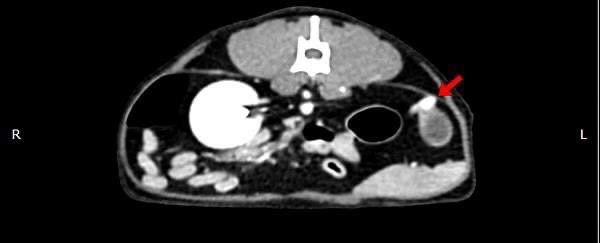

• 狗狗後腳癱瘓也有可能是血栓 不一定是骨骼神經肌肉問題喔

狗狗後腳癱瘓也有可能是血栓 不一定是骨骼神經肌肉問題喔